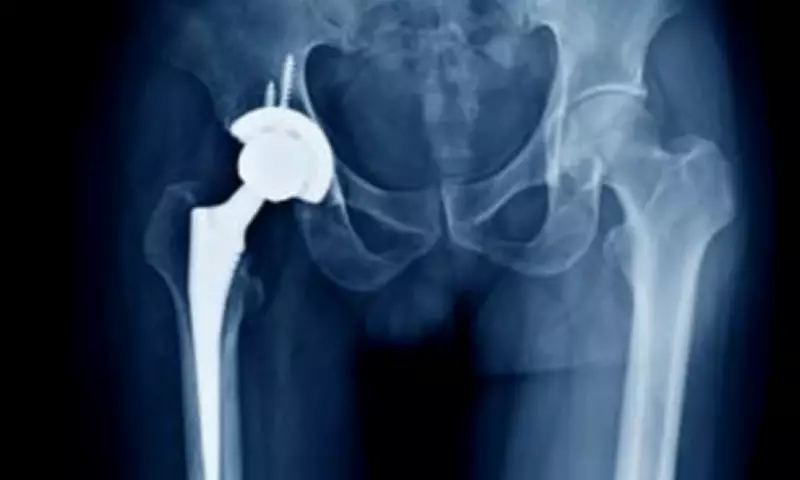

Bone cement acts as a strong grout, filling the space between metal implants and patient bone to create a stable bond. With an estimated 110,000 hip replacement surgeries performed in 2023/24, and 120,000 hip and 96,000 knee procedures recorded that year, the two-month hold-up could affect thousands of patients. Many have already endured lengthy waits, with parliamentary data from February 2025 showing 31,323 patients waiting for hip replacements (median wait 24.7 weeks) and 49,500 for knee replacements (average wait 28.7 weeks).

The affected products include cements used for standard joint fixation and those with antibiotics for infection management in revision surgeries. In revision procedures, cement can help maintain joint space and deliver high local antibiotic doses before a new implant is inserted. The NHS has issued immediate guidance to hospitals to ensure trauma and urgent care continue safely, enable use of alternative suppliers, and support prioritisation of orthopaedic waiting lists based on patient needs.